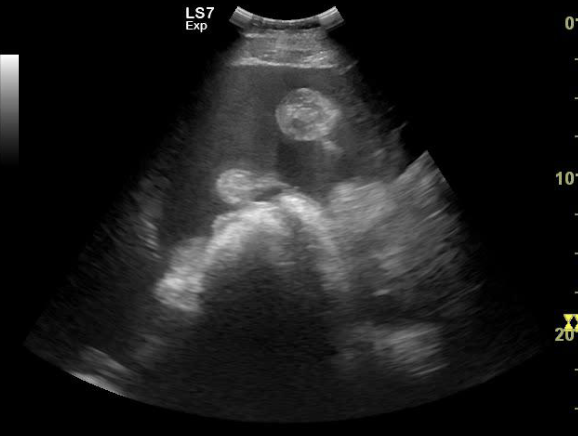

what does this peritoneal US show?

tadpole looking structure = intestine, normal to see the round part, but wouldnt usually see the mesentery (tail of tadpole)